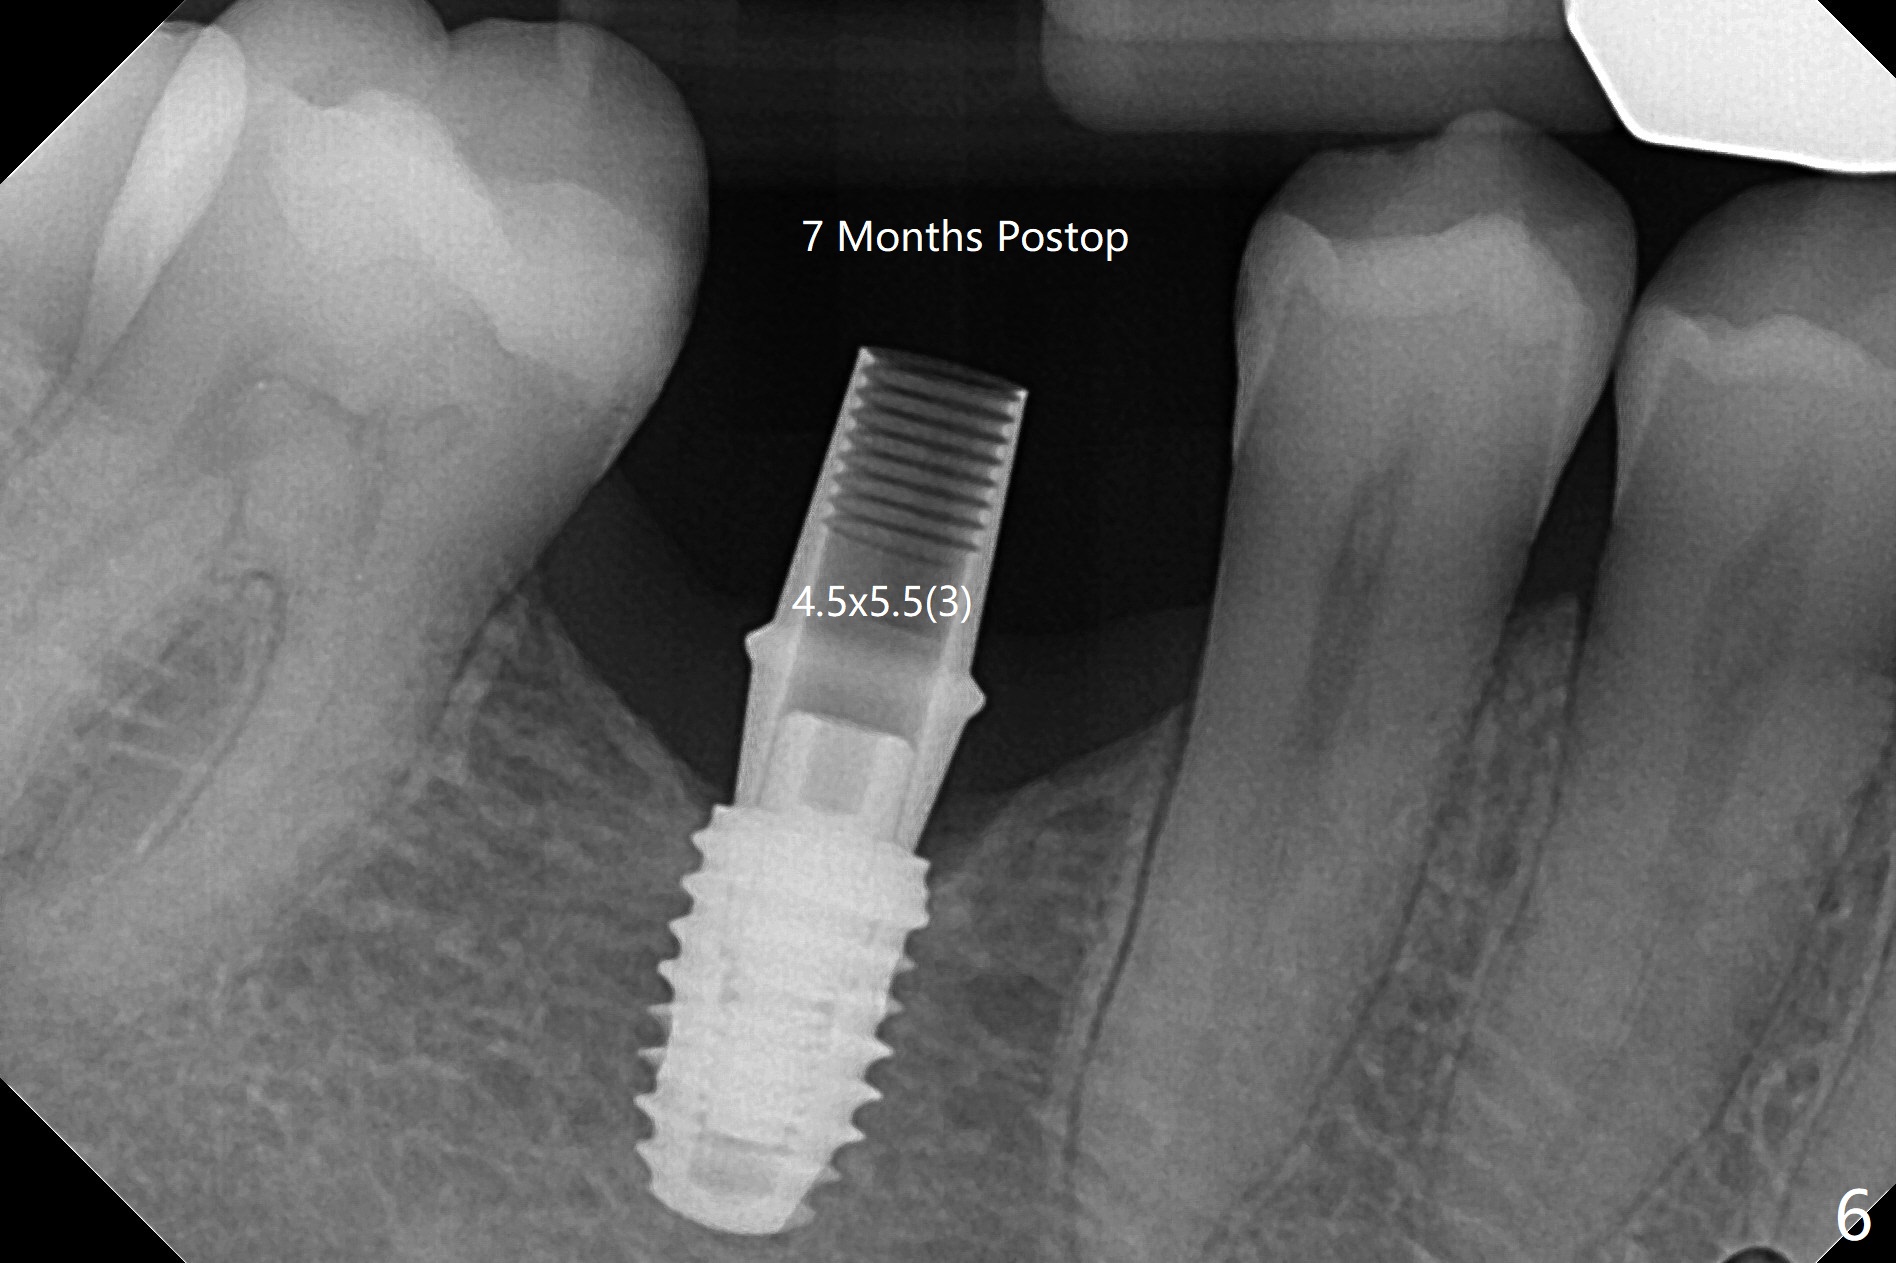

术后7个月左下4毫米修复基台无法就位(图四:箭头),局麻下使用4.6毫米Profile钻头后(去除软硬组织阻挡),4.5毫米修复基台顺利就位(图五)。右下第一次手术已经应用Profile钻头,牙槽嵴吸收,所以放置4.5毫米修复基台没问题(图六)。第一次手术应该使用Profile钻头。